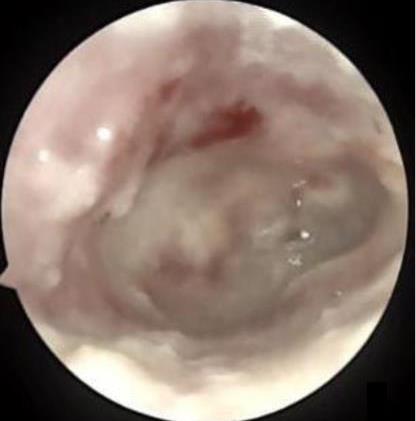

• 医用生物蛋白胶应用于耳内镜下鼓膜修补术的临床疗效

摘要:目的 分析医用生物蛋白胶应用于耳内镜下鼓膜修补术的临床疗效。方法 回顾性分析2022年10月-2023年10月该院收治的60例单纯鼓膜穿孔患者的临床资料,根据手术方法不同,将患者分为研究组和对照组,各30例。研究组术中使用医用生物蛋白胶粘合残余鼓膜和修补材料;对照组术中采用明胶海绵覆盖修补鼓膜。观察两组患者术后的鼓膜愈合情况(鼓膜愈合率、愈合时间、干耳时间和外耳道上下径)和并发症发生情况;于手术前后,采用纯音测听法(500、1 000、2 000、4 000 Hz),测量两组患者气导阈值,观察听力改善程度;采用视觉模拟评分法(VAS)评分,评估患者术后疼痛程度。结果 两组患者术后鼓膜愈合率、愈合时间、外耳道上下径和并发症发生率比较,差异均无统计学意义(P > 0.05)。研究组术后平均气导听阈明显低于对照组,差异有统计学意义(P < 0.05)。研究组术后干耳时间短于对照组,术后第1天疼痛VAS评分明显低于对照组,差异均有统计学意义(P < 0.05)。结论 医用生物蛋白胶应用于耳内镜下鼓膜修补术,可有效地降低气导听阈,缩短干耳时间,减轻患者疼痛,且不增加并发症发生率,值得临床推广应用。